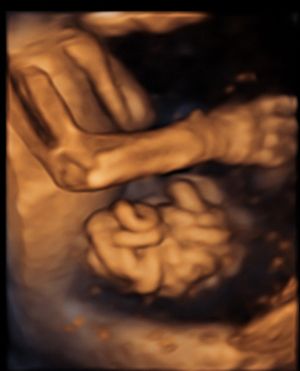

Im Rahmen des Ersttrimester-Screenings untersuchen wir die Organe des Feten mittels Ultraschall. Dabei machen wir auch gerne ein Bild für Sie.

Obwohl der Fet zu diesem Zeitpunkt erst zwischen 5 und 8cm groß ist, lassen sich bereits etwa die Hälfte aller schwerwiegenden Fehlbildungen erkennen bzw. ausschließen. Sollten wir eine Auffälligkeit sehen, werden wir mit Ihnen den Befund und das weitere Vorgehen ausführlich besprechen.

Die eigentliche Organuntersuchung findet um die 20.SSW (zweites Screening) statt. Das Ersttrimester-Screening und das zweite Screening sind sich ergänzende Untersuchungen und ersetzen sich gegenseitig nicht.